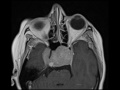

Pituitary Macroadenoma

These images show a very large avidly enhancing mass expanding the sella and extending into the suprasellar cistern resulting in severe mass effect on the optic apparatus and third ventricle. The mass also extends posteriorly splaying the midbrain. Centrally in the suprasellar mass there is T1 hyperintensity and increased susceptibility compatible with hemorrhage. There is evidence of invasion into the cavernous sinuses with tumor encasing the cavernous and supraclinoid internal carotid arteries without narrowing them. There is also mass effect of the anteromedial right temporal lobe secondary to marked tumor expansion of the right cavernous sinus. These findings are compatible with a giant pituitary macroadenoma with internal hemorrhage which was confirmed on pathology. Differential considerations at the time of imaging included papillary subtype craniopharyngioma and a mass arising from the clivus or sphenoid sinus which were considered less likely. This patient undoubtedly presented with visual changes. Peak incidence is in young adults 20-40 year old.